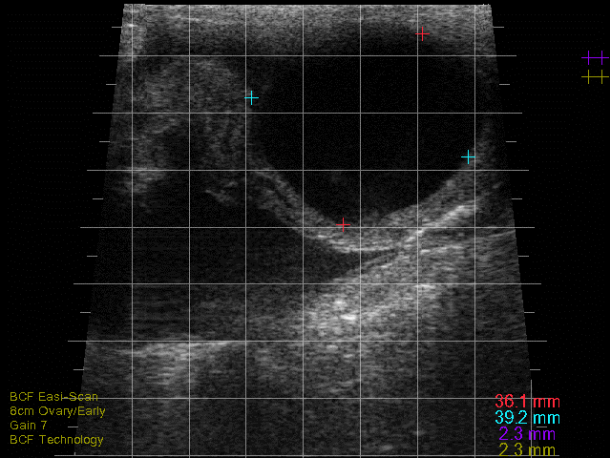

The ovaries of normal cyclic cows can contain numerous follicles and typically one (or occasionally two) corpus luteum (CL) of differing morphological appearance depending on their stage of development.

Follicles are easily detectable on the ovary and they appear as round, black (anechoic) fluid-filled structures2. Cows can have typically two to three follicular waves during an oestrous cycle3. Small follicles (<5mm) can be seen clustered throughout the ovaries and, as they are recruited and then selected, they will grow until one (or occasionally two) becomes dominant which occurs at around 8-10mm, with ovulatory follicles measuring 16-24mm by the time of ovulation2,3. Due to continuous process of follicular waves, it is common to find large follicles (>8mm) on the ovaries (with the exception of the first few days after ovulation) and it is thus difficult to rely on size or growth alone to predict ovulation2.

Detection of a CL is a useful finding for a practitioner as it indicates that a cow is cyclic. CLs typically appear as a solid, moderately echogenic (grey-like) structures on the ovary with a round appearance2. However, it is common for CLs to have an irregular or lobulated shape, particularly if there is an ovulation point2. Many will develop with a central cavity and this is commonly seen in the first 10 days of the cycle with up to 30-50 per cent of CLs being cavitated2. CLs vary in size and structure depending on the stage of the cycle. In the early luteal phase (days one to five), the CL will appear as a small (~12-14mm), soft structure with a developing echogenic rim and often a cavity2. From the mid-luteal phase (days eight to 16), the CL is larger (20-25mm) more well-defined and often solid, although some cavities within CLs can persist throughout the cycle and even into pregnancy, with the vast majority filling in by 30 days of gestation2.

Follicular cysts are typically large, thin-walled (<2-3mm), round, black structures that are often single but can be multiple (see Photo 1)2,4. Traditionally, follicular cysts were defined by being greater than 25mm in diameter and persisting for longer than 10 days but recent work would indicate that follicular cysts can be present and only measure 16-17mm in diameter2. Cows with follicular cysts will have low peripheral progesterone concentrations and typically present anoestrous but can be nymphomaniacal if the cyst is actively secreting oestradiol4. However, that stated, follicular cysts are still dynamic structures which can luteinise (forming a luteal cyst), or become inactive and regress. In situations where they have begun to regress, the cystic structures can be noted in cows who have started to cycle again (i.e., some of these cows will have CLs) or even those cows who have become pregnant.